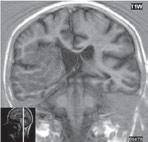

Obr. I.1.2c Ageneze corpus callosum, frontální rohy postranních komor mají tvar rohů na Vikingské helmě, kraniálně uložená III komora

Obr. I.1.2e Ageneze corpus callosum, frontální rohy postranních komor mají tvar rohů na Vikingské helmě, kraniálně uložená

III komora, Probstovy provazce (šipka)

konvergentnímu průběhu) a jejich oddálení, časté rozšíření okcipitálních rohů – colpocefalie, někdy středočárový lipom, cystu. Koronální řezy ukážou rozšíření frontálních rohů postranních komor, III. komora je situována vysoko mezi postranní komory, tvoří jakoby trojzubec, který někteří autoři přirovnávají k přilbě Vikinga. Není patrné septum pellucidum. Častá je přítomnost středočárového lipomu nebo cysty.